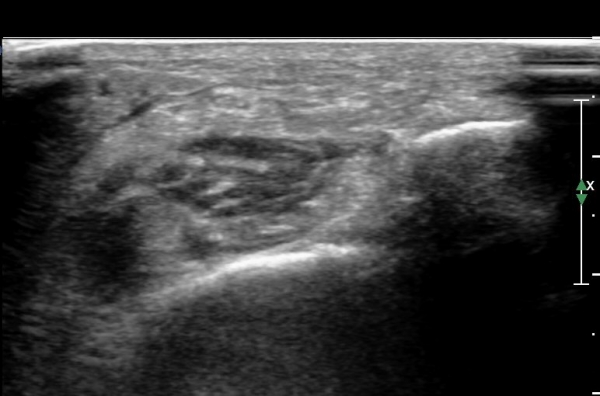

¾Æ·§´Ù¸® ¿ÜÃø Ⱦ´Ü¸é°Ë»ç¿¡¼ Àåºñ°ñ±Ù°ú ¹ß°¡¶ô½ÅÀü±Ù »çÀÌ¿¡¼ õºñ°ñ½Å°æÀÌ Á¤»óÀûÀ¸·Î °üÂûµÈ´Ù(»çÁø 1, , 2, 3, 4, 5).

¾ÕÂÊ ¸»´Ü °æ°ñºñ°ñ°üÀý ¾à 5cm ±ÙÀ§ºÎ Ⱦ´Ü몀°Ë»ç ½Ã õºñ°ñ½Å°æ Àü¸é¿¡ Àú¿¡ÄÚ ³¶Á¾¿¡ ÀÇÇÑ ½Å°æ ¾Ð¹ÚÀÌ °üÂûµÈ´Ù(ÀÌ °üÂûµÈ´Ù(»çÁø 6, 7).

¸»´ÜÀ¸·Î °¥ ¼ö ·Ï ³¶Á¾ÀÌ Ä¿Áø°í õºñ°ñ½Å°æ ¾Ð¹ÚÀº ½ÉÇØÁø´Ù(»çÁø 8).

³¶Á¾À» Á¾´Ü¸éÀ¸·Î °üÂûÇÏ´Ï ³¶Á¾ÀÌ ¸»´Ü °æ°ñºñ°ñ°üÀý¿¡¼ À¯·¡µÊÀÌ È®ÀεȴÙ(»çÁø 9).